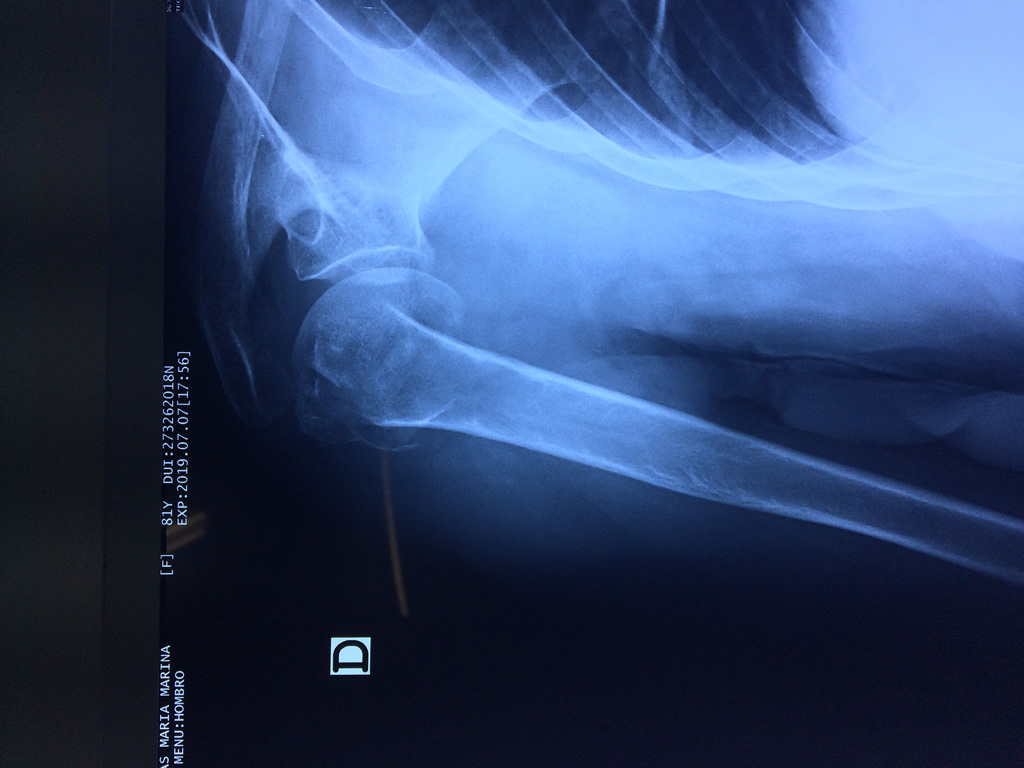

La principal articulación del hombro es la que une la cabeza del húmero con la escápula, recibe el nombre de articulación escapulohumeral y presenta dos superficies articulares, una de ellas corresponde a la cabeza del humero que tiene forma semiesférica y la otra es la cavidad glenoidea de la escápula, estas superficies están recubiertos por cartílago que permiten un movimiento suave e indoloro.

Exteriormente una envoltura de tejido blando circunda el conjunto, es la llamada cápsula articular que está reforzada por varios ligamentos que le dan estabilidad e impiden que los huesos se desplacen más allá de sus límites fisiológicos. Un conjunto de músculos y sus tendones se unen a las superficies de los huesos y hacen posible la movilidad de la articulación, entre ellos es muy importante el manguito rotador formado por cuatro músculos que proporcionan movilidad y estabilidad al hombro.